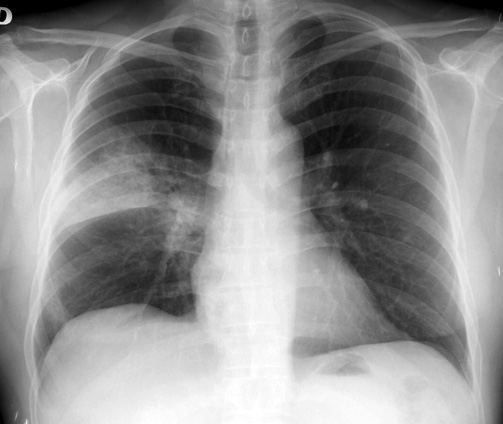

Ojo de Markov número setenta y ocho - noviembre 2018 Sacyl, 12 de diciembre de 2018 La Neumonía adquirida en la comunidad (NAC) es una infección aguda del parénquima pulmonar que se manifiesta por signos y síntomas de infección respiratoria de vías bajas en pacientes no hospitalizados o institucionalizados y que no han sido ingresados en un hospital en los 14 días previos al inicio de los síntomas. Se excluyen las neumonías que afectan a pacientes con cáncer e inmunodeprimidos